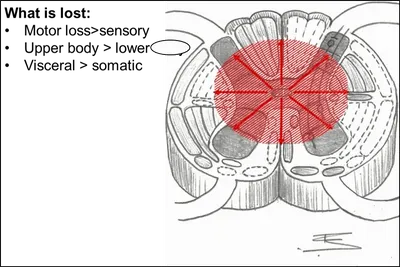

2) Acute hyperextension injury -> Central cord syndrome

a) frequently in pre-existing congenital stenosis/ 50% eventually recover to ambulate independently / recovery of U/Ex function – POOR, absent fine motor control / bowel & bladder control is frequently recover

b) weakness : UE>LE / variable sensory loss below lesion

@ 보통 C5-7에 호발하는데 척수 중심부에 출혈이나 부종 등이 발생된 경우 나타남